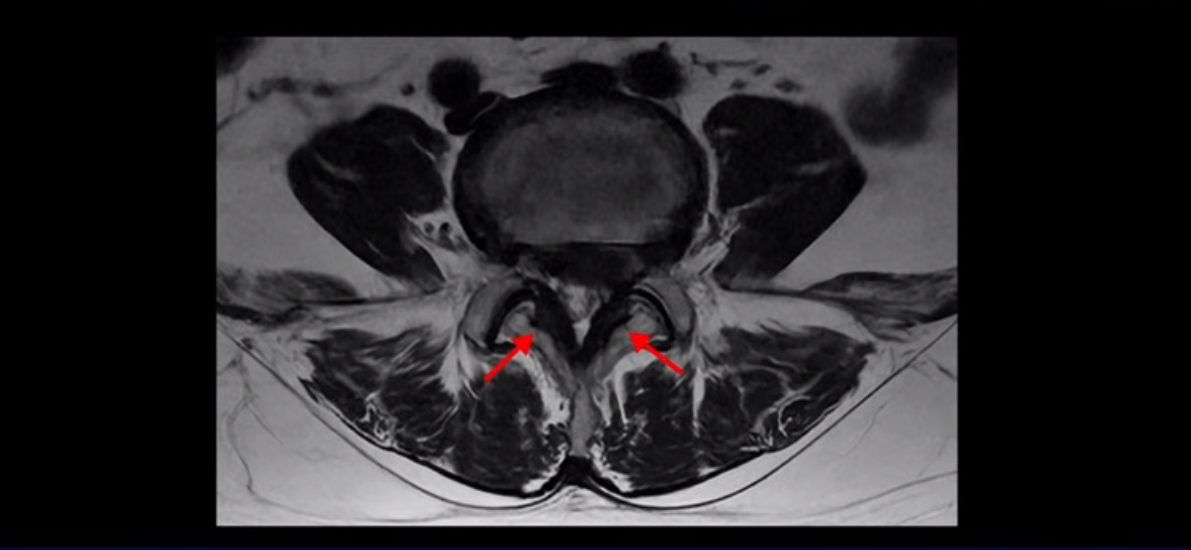

단면을 보면 디스크 수핵은 왼쪽으로 심하게 밀려 나와 있고

좌우 뒤쪽에는 황색 인대가 두꺼워져 있습니다.

앞에서는 디스크 수핵이 신경 공간으로 침범하고 뒤에서는 두꺼워진 인대가 신경 공간을 좁히고 있습니다.

이렇게 신경 공간이 좁아진 것을 협착이라고 합니다. 왼쪽으로 신경 구멍이 더 좁아져 있으니까 처음에는 왼쪽 엉덩이와 다리가 아팠는데 몇 년 동안 주사 맞으면서 버티다 보니까 오른쪽 다리까지 아프게 됩니다. 결국 양쪽 다리가 너무 아파서 5분 걷기도 힘들어지게 됩니다.

걸을 수 있는 거리는 점점 짧아지고 왼쪽 발의 근육이 빠져서 신발이 헐거워졌다는 얘기 들으셨죠? 이분 MRI를 보면

디스크 파열은 심해 보이나 신경 구멍이 좁아지는 협착증으로 보자면 저희 다른 치료 후기에 나오시는 협착증 환자분들의 MRI에 비해 신경 구멍은 넓은 편입니다. 그래서 신경이 정말 심하게 눌릴 때 나타나는 다리의 힘 빠짐 증상은 없었고 통증, 즉 아프다는 증상을 제일 심하게 호소하셨습니다.